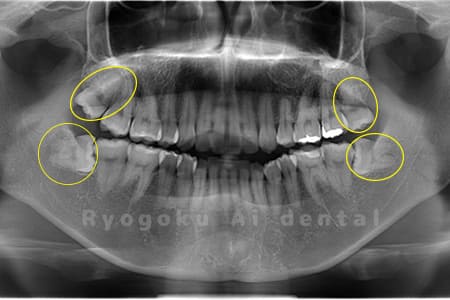

Case01

- 原因

- 水平埋伏智歯

- 治療内容

- 下顎の水平埋伏智歯を抜歯

<リスク・副作用>

手術後は痛み、腫れ、痺れなどの副作用が生じる場合があります。